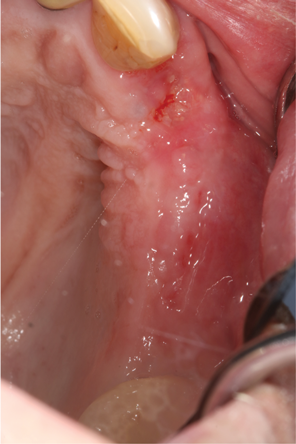

Fig 14. Two-week postoperative healing at maxillary left quadrant lateral ridge augmentation.

Figure 14